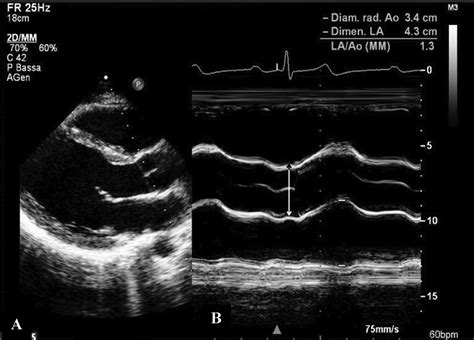

• Echocardiogram: This non-invasive test uses sound waves to create images of the heart and aorta, allowing the healthcare provider to measure the size of the aortic root and assess its function.